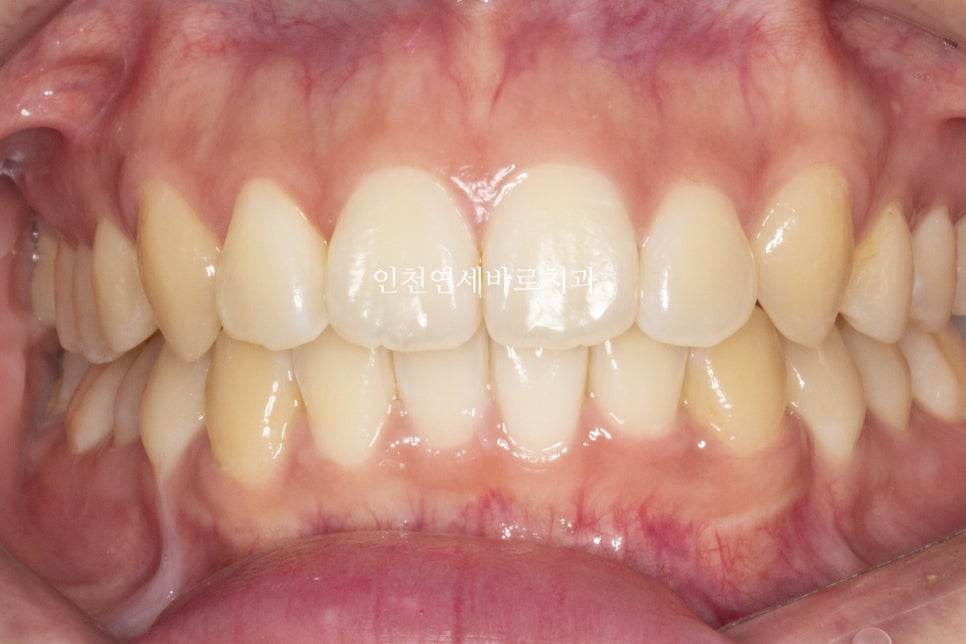

치료 후 1년이 지난 모습입니다.

중심선 및 교합 모두 잘 유지되고 있습니다.